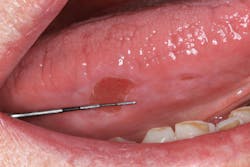

Clinical assessment revealed overall red, inflamed tissue throughout the oral cavity. Most notably present were large, ulcerlike lesions on the right and left lateral borders of the tongue (figures 1 and 2). The edges were well-defined and the red center slightly concave and very tender to palpation. Further, the vestibular tissue, upon the slightest touch, sloughed and hemorrhaged easily. Angular cheilitis was observed, and opening was painful (figure 3).